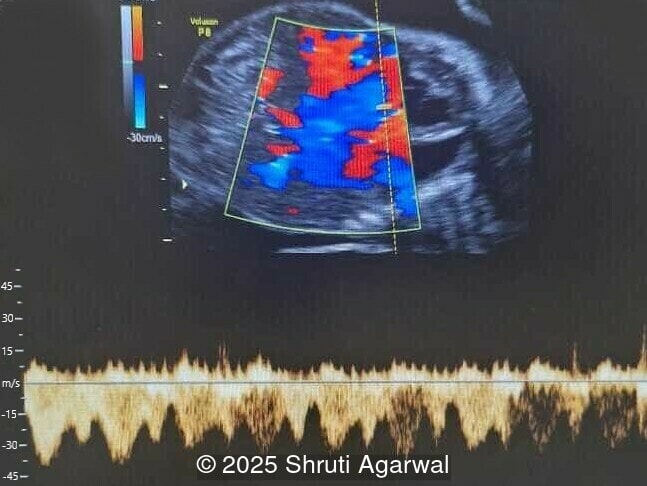

We present a case of fetal anemia due to a giant chorangioma.

• Image 1,2: Large placental tumor is identified with internal vascularity

Prenatal diagnosis depends on ultrasound, however, chorangioma can cause an increase in maternal serum alpha-fetoprotein [3]. Ultrasound examination reveals a hypo- or hyperechoic, well-circumscribed mass, which is usually located underneath the chorionic plate near the umbilical cord insertion, and often protrudes into the amniotic cavity. Color Doppler demonstrates large vascular channels around and within the tumor [6,9]. In cases of giant chorangiomas, echocardiography should be performed to assess cardiac function and measure fetal middle cerebral artery peak systolic velocity for diagnosis of fetal anemia. Regular ultrasounds with Doppler studies are used to monitor tumor size, fetal growth, amniotic fluid volume, and signs of fetal anemia or heart failure. The frequency of exams is based on tumor size and associated complications. With small tumors, assessment may occur every 3-4 weeks, whereas in large tumors, the ultrasound scan may be done every 1-2 weeks [3]. These regular assessments can diagnose conditions that require intervention, such as polyhydramnios, hydrops, or hemolytic anemia.

Besides the histopathology examination, ultrasonography and particularly color Doppler sonography is helpful in differentiating chorangioma from other placental pathologies such as hematoma, infarcts, intervillous thrombosis, partial mole, leiomyoma, and placental teratoma. The pattern of blood flow to the tumor can assist in differentiating between different placental tumors [3,10].